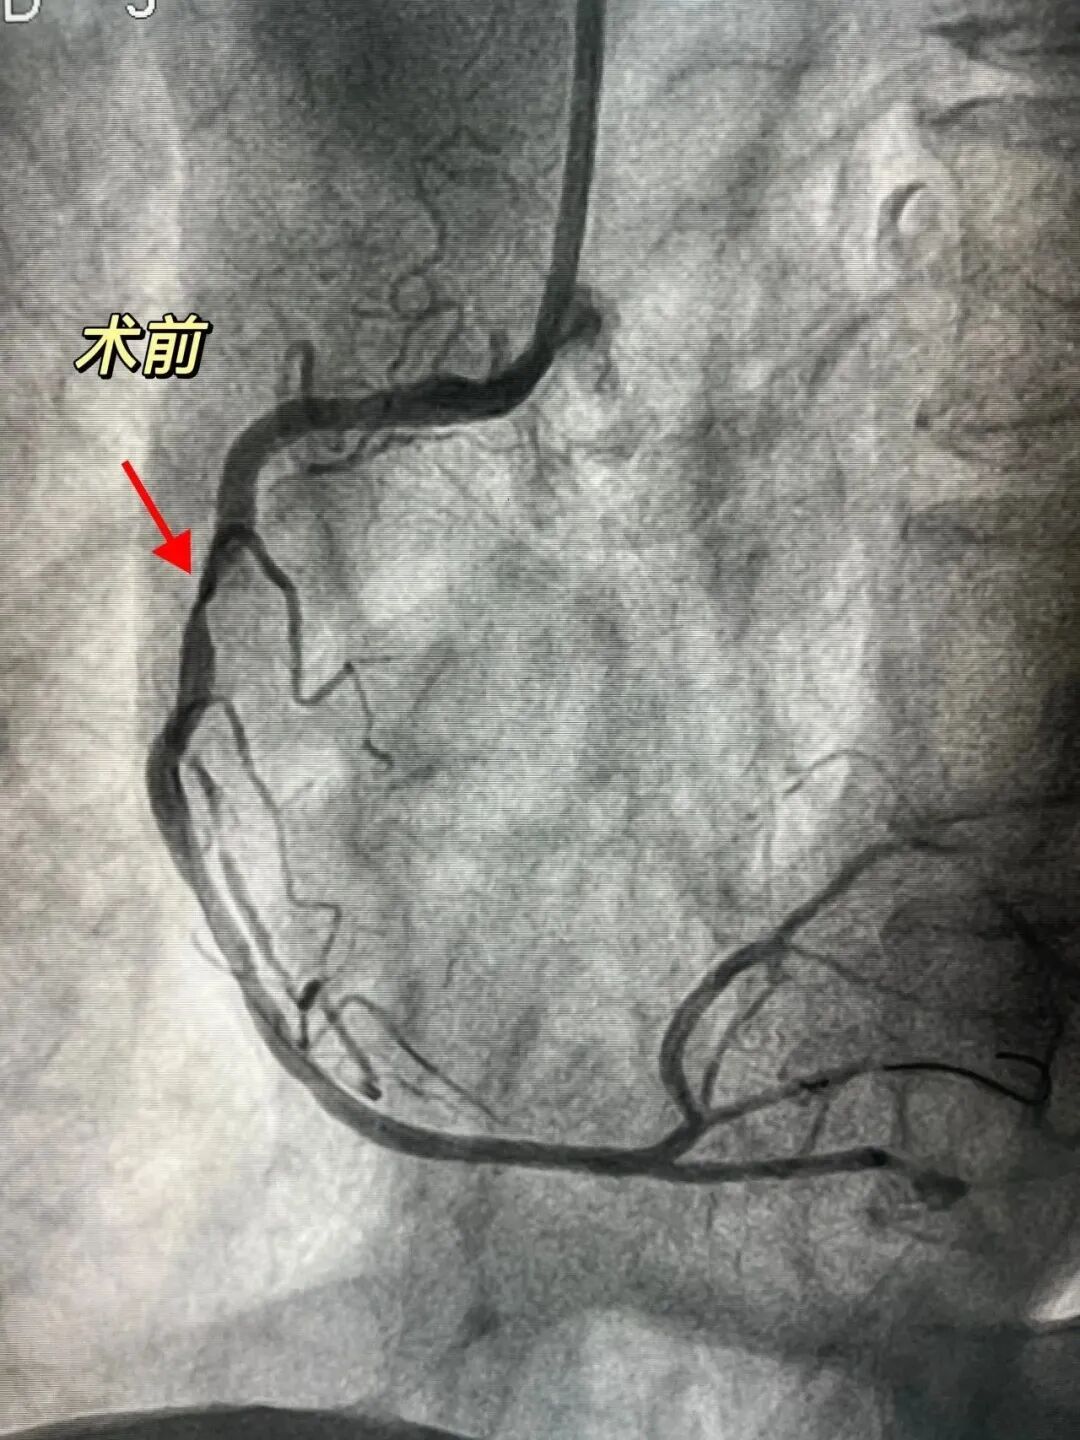

“难点”被击破后,团队顺利为患者植入支架一枚,复查造影及IVUS提示新植入的支架扩张充分,贴壁良好。术后,患者即刻表示胸闷、胸痛症状均得到缓解。

该新技术与治疗肾结石的声波技术原理相似,主要通过对球囊进行低压扩张,向病变处发射非聚焦、脉冲式的冲击波,安全地碎裂浅、深层钙化,改善血管顺应性,使得植入支架后能够膨胀良好,最大程度减少严重血管并发症的发生。“由于其是靠声压力波实现球囊内约50atm扩张力的震波效果,而非靠球囊本身的压力来扩张血管,因此这种手段一方面能够使钙化斑块碎裂,一方面又对周围软组织影响很小,具有‘打硬不打软‘的特性,所以它对于治疗钙化病变具有‘奇效’,并且安全性很高。”黄剑锋主任介绍道。